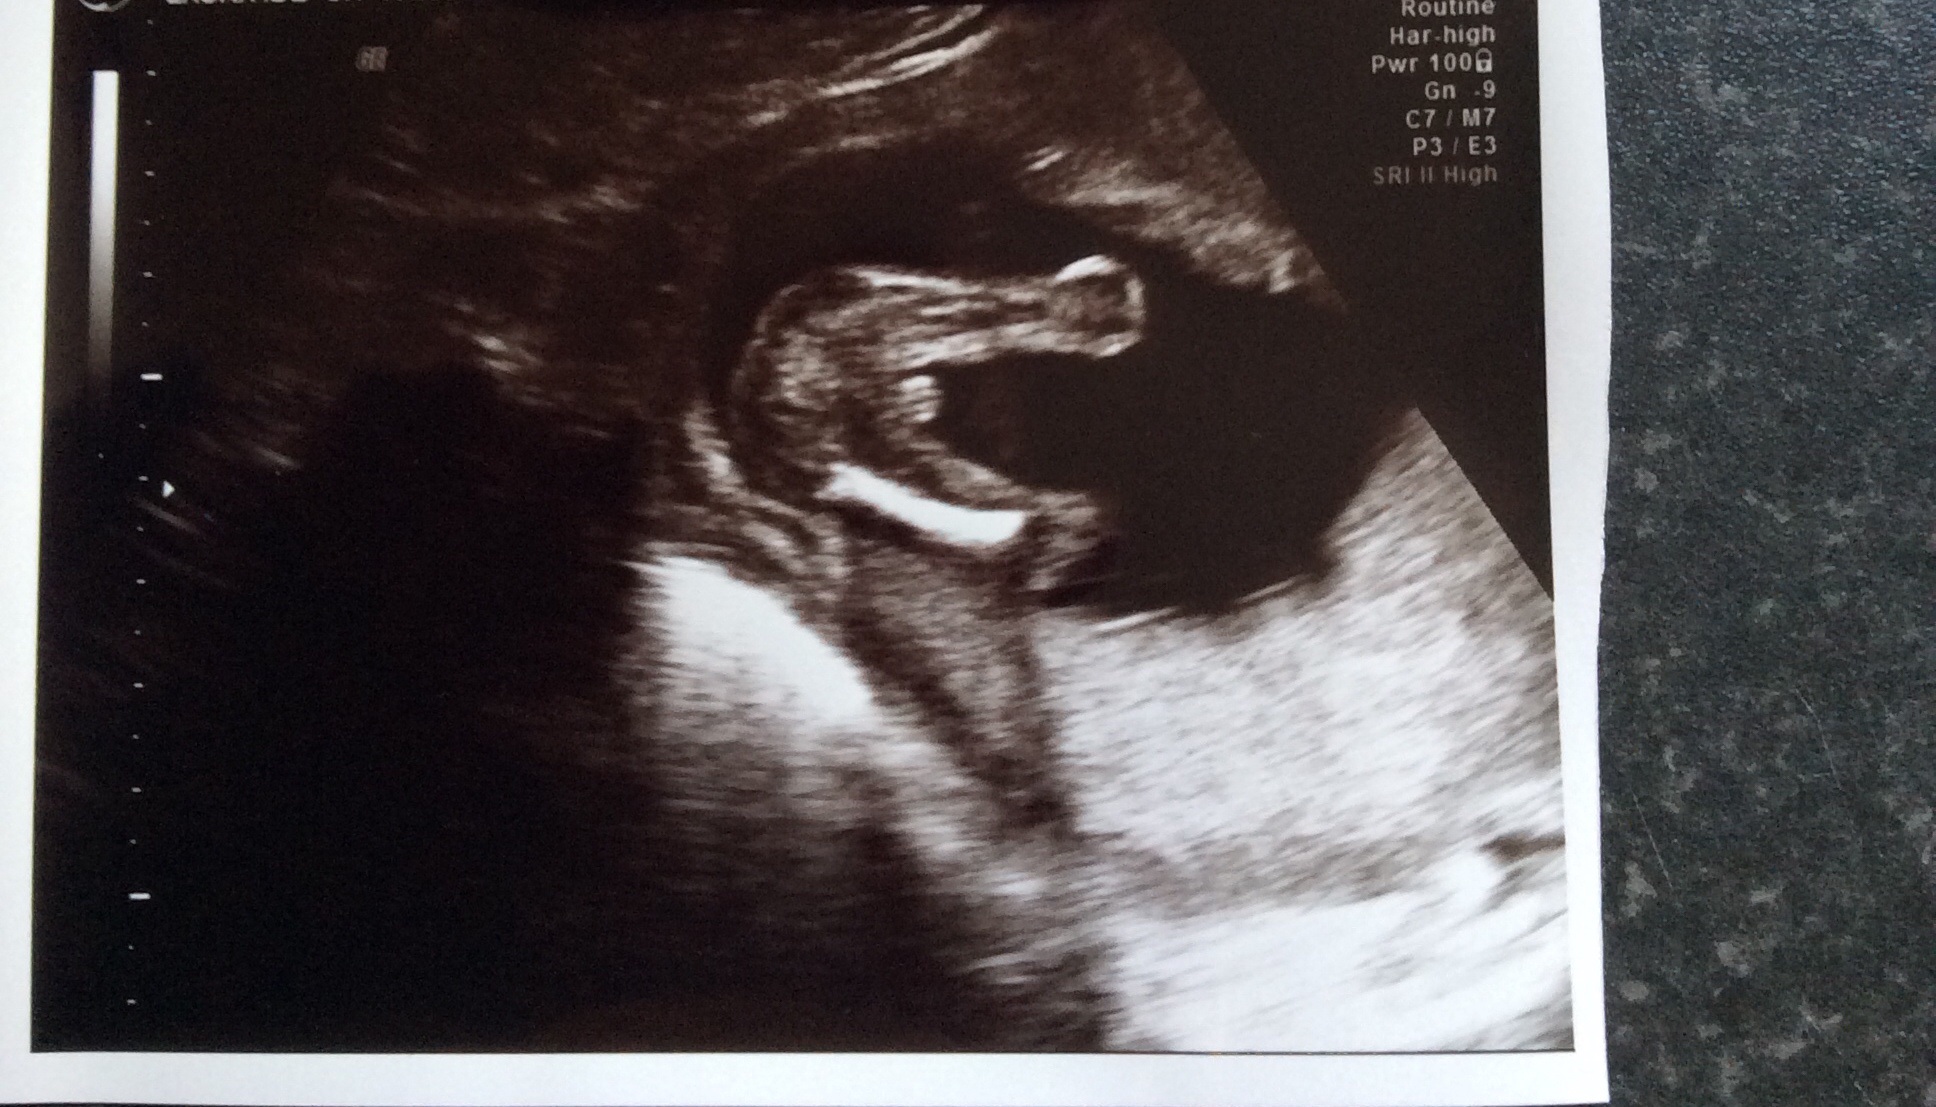

Been told boy but potty shot 16+3 I'm not so sure??

When we got called back in she had another look but still struggled she was saying I'm going to have to get you back in, then she got a picture and said boy! We have 3 photos all together?

I suffered bad GD last time and don't want that this time that's partly why we gave had this scan! At the end of the scan the lady said baby was very difficult and I think you should just make sure it's defiantly a boy when you go to your 20 weeks scan. I thought that was a lil odd as never had a tech say that to me before!

Anyways this is the scan potty shoots! The first one she said was boy